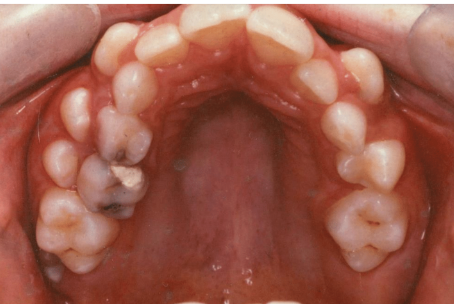

what age is this pt

10/11/12 years

tx option for retained primary teeth on RHS

extraction

in which caries risk category would you place this pt

and why (3)

high risk

existing restorations

new carious lesions

early loss of primary tooth (64)

which radiographs would you take to further investigate caries in posteiror teeth

bitewings

bitewings confim no caries in FPM

what preventative tx would you provide

fissure sealants